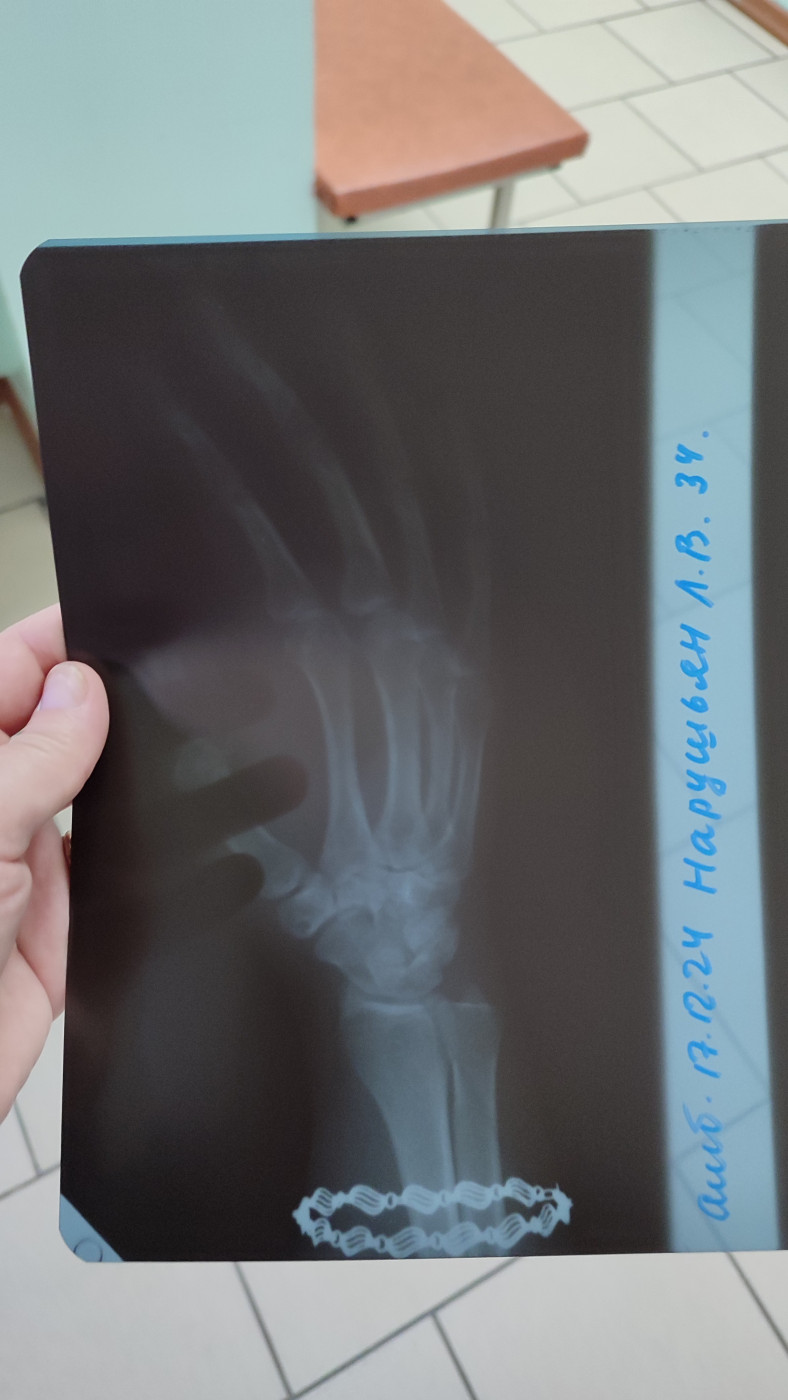

После удара по руке, болит уже второй месяц